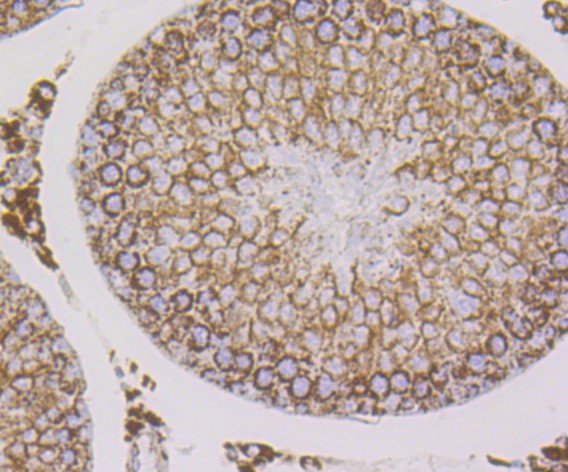

Immunohistochemical analysis of paraffin-embedded rat testis tissue using anti-Cpn10 antibody. The section was pre-treated using heat mediated antigen retrieval with Tris-EDTA buffer (pH 8.0-8.4) for 20 minutes.The tissues were blocked in 5% BSA for 30 minutes at room temperature, washed with ddH2O and PBS, and then probed with the primary antibody (ET7108-67, 1/50) for 30 minutes at room temperature. The detection was performed using an HRP conjugated compact polymer system. DAB was used as the chromogen. Tissues were counterstained with hematoxylin and mounted with DPX.